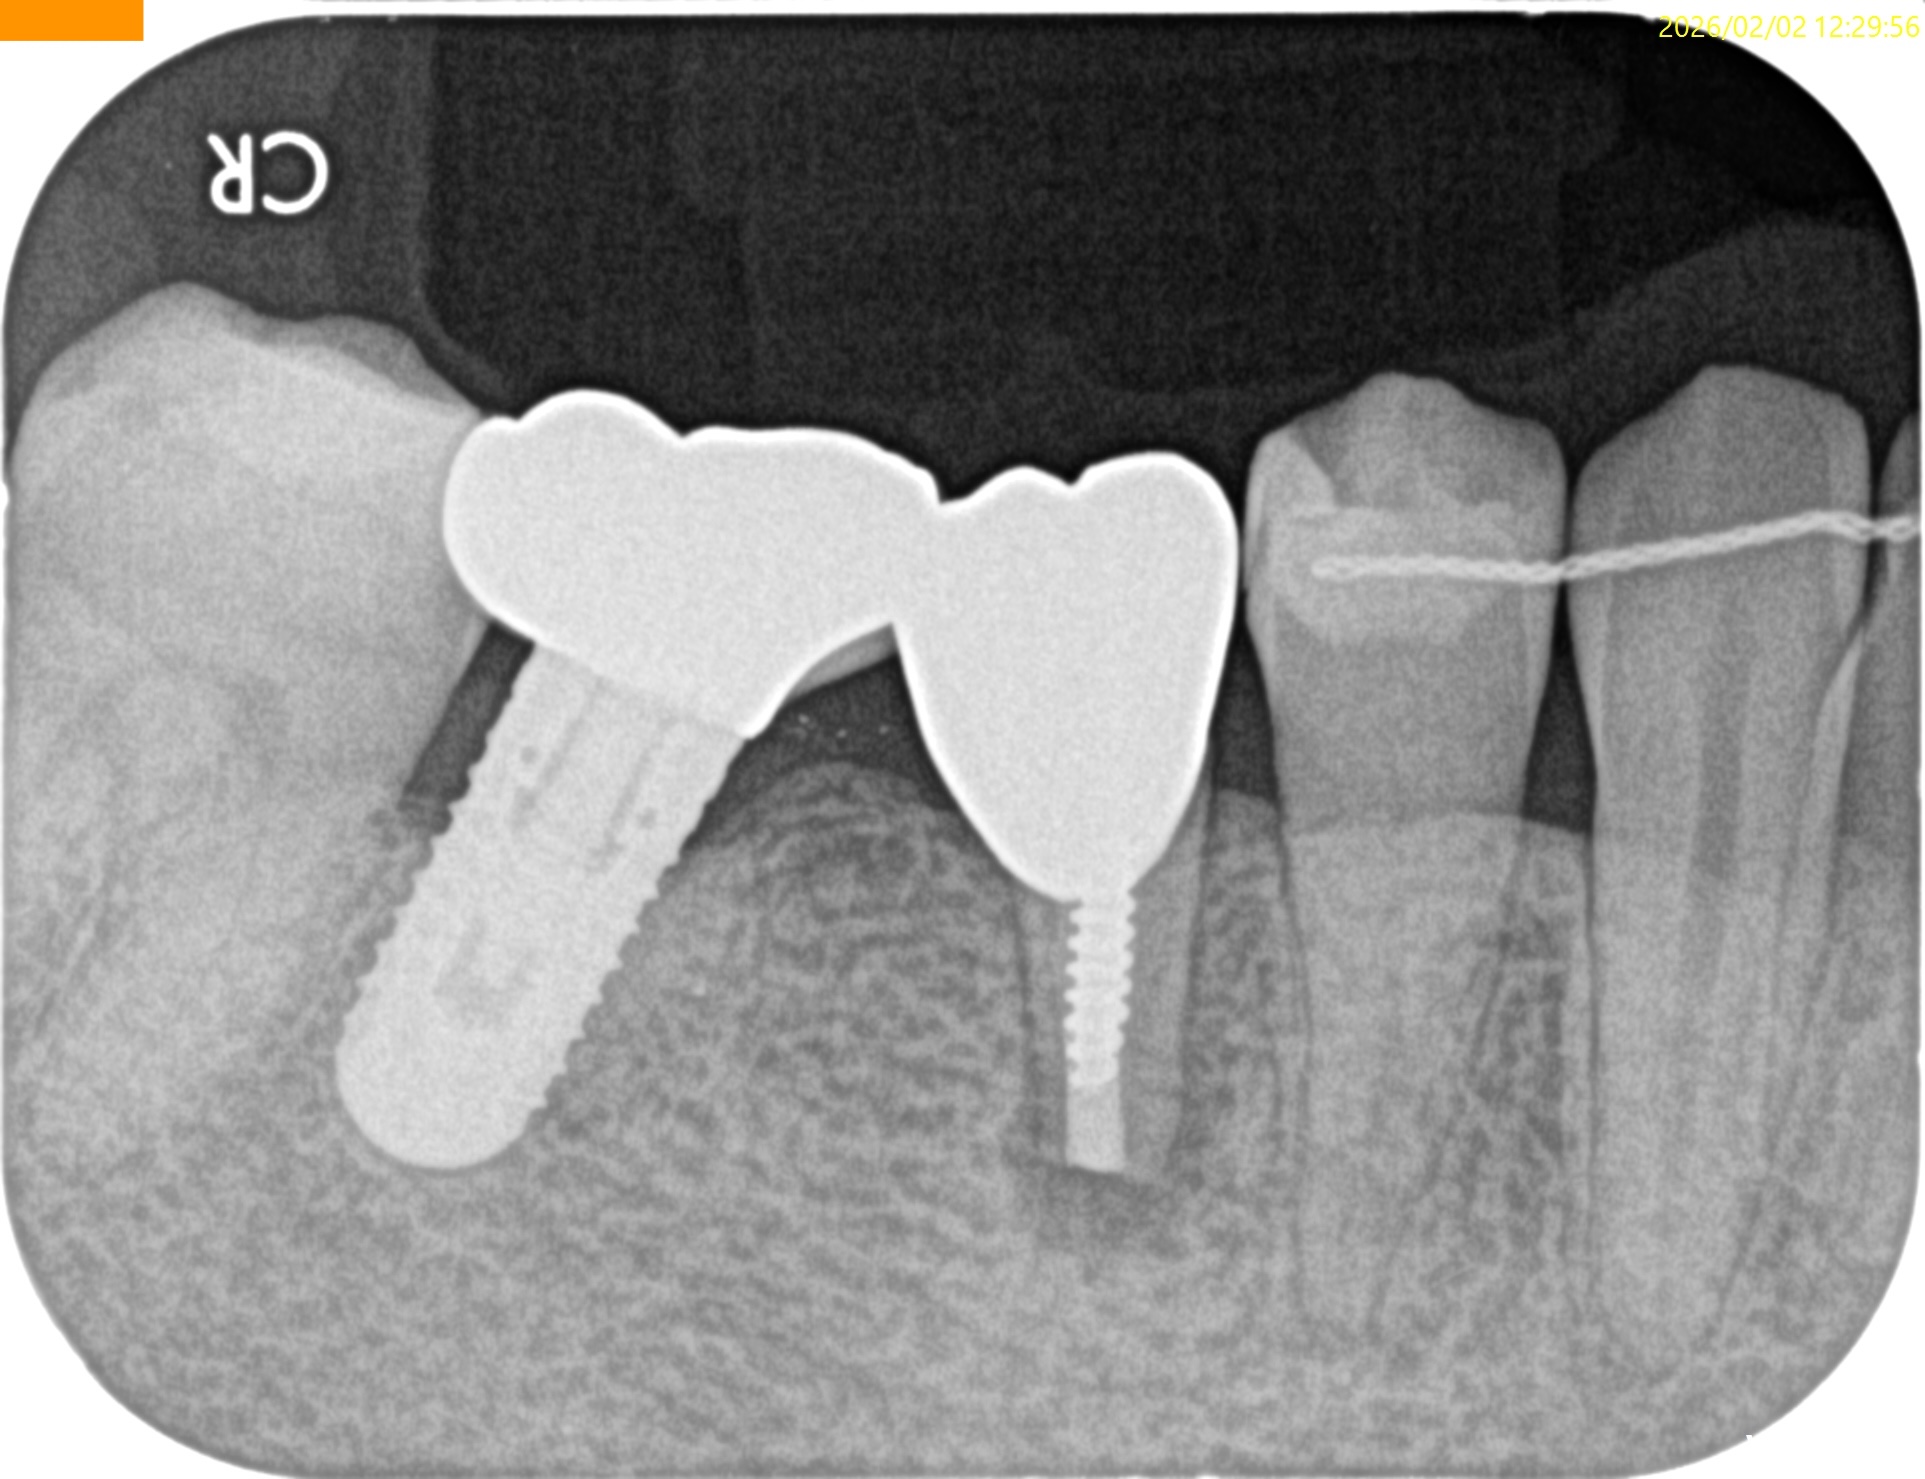

術後にPAを撮影した。

問題はないと思われる。

歯牙を再植した。